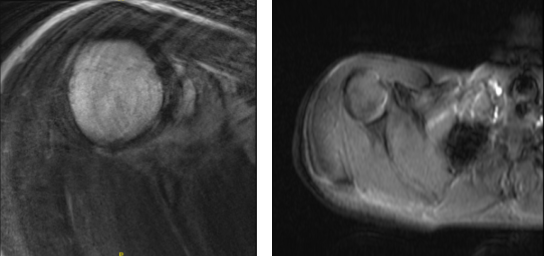

After two weeks post-operative, MRI was presented. Right shoulder MRI showed AC joint sprain and Suspected calcific tendinitis of the supraspinatus tendon.

Repeat X-ray or CT correlation is recommended for definitive assessment. Reviewed the left shoulder MRI, Focal low-grade partial tear of the anterior supraspinatus tendon and mild subacromial subdeltoid bursitis found.

MRI-3T Right Shoulder Non-contrast

MRI-3T Left Shoulder Non-contrast